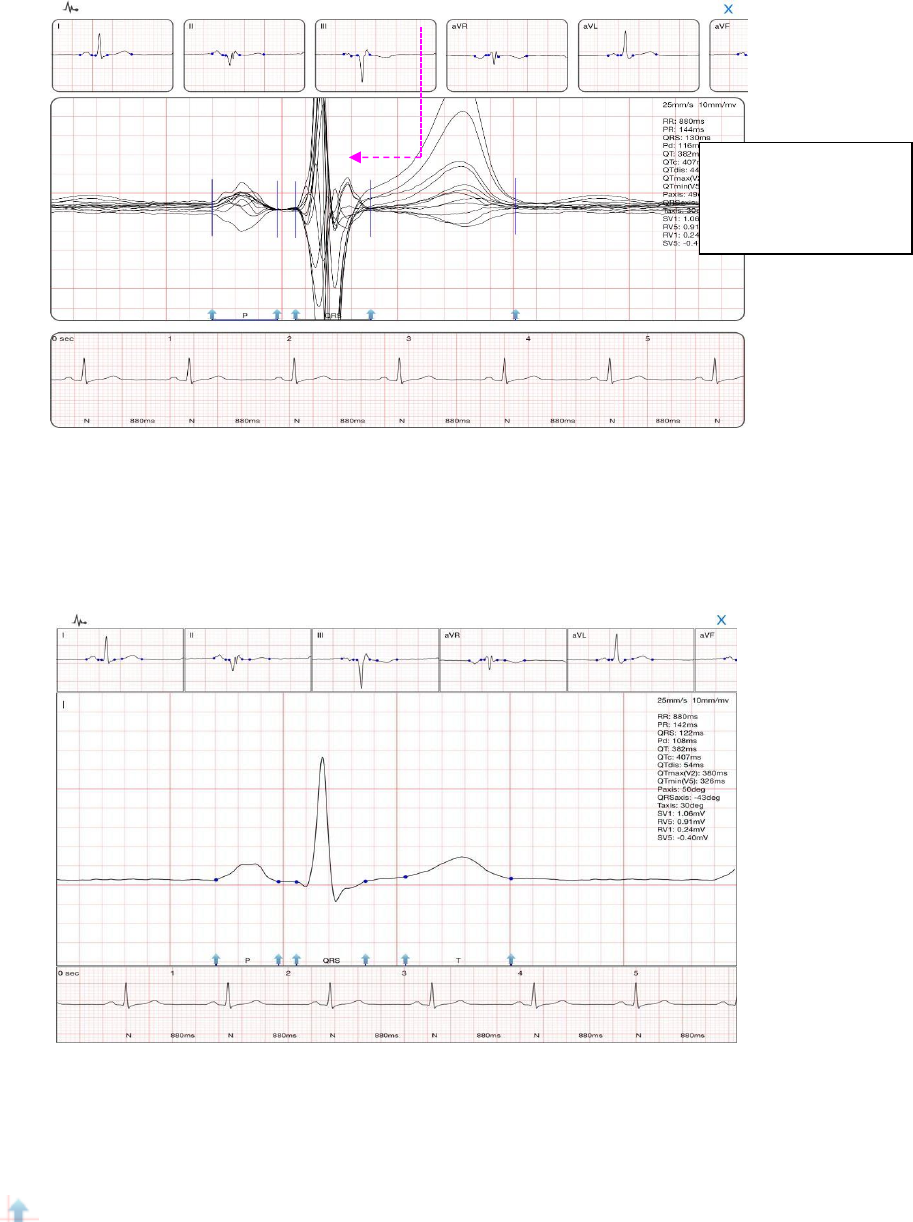

“QRS”window

In "QRS" window, the bottom of the report shows single lead waveform. Click on a lead to

view the waveform (as below).

QRS window of Single Lead

In the operating area, slide with two fingers to call out ruler to measure the waveform (Figure:

blue dotted lines and numbers); adjust the locating point of QRS wave by dragging the blue

arr

ow